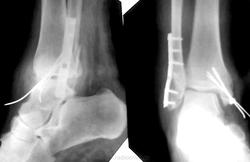

Пациентке 50 лет, в марте 2011 получила бытовую травму, при поступлению в одну из ЦРБ Нижегородской области был диагносцирован трехлодыжечный перелом, наружный подвывих стопы (рентгенограммы 1). Поскольку боковая рентгенограмма сделана с ротацией, никто не обратил внимания на передний отдел метаэпифиза б/берцовой кости. Пациентке налажено скелетное вытяжение (рентгенограммы 2,3), на боковом снимке видно повреждение переднего отдела метаэпифиза, но внимание на это не обращается, выполняется стандартный остеосинтез наружной и внутренней лодыжек (рентгенгограммы 4), опять же ни о кого не возникает никаких вопросов, а именно: почему дисконгруэнтна суставная щель, стопа в переднем подвывихе и в эквинусе. В августе пациентка приходит на контроль, и уже отчетливо виден дефект переднего отдела метаэпифиза б/берцовой кости, смещение костного фрагмента метаэпифиза кпереди и передний вывих стопы, но никаких мероприятий не проводится. Вчера, 9.02 пациентка все же доходит до нашего института, и мы видим такую картину (рентгенограммы 5,6): дефект переднего края дистального метаэпифиза б/берцовой кости, костный фрагмент смещен кпереди, некротизирован (фактически это секвестр), стопа в положении переднего вывиха, разрыв дистального межберцового синдесмоза, нестабильность металлоконструкций в б/берцовой кости (отчетливо видна резорбция), асептический некроз блока таранной кости. Прогноз неблагоприятен: артродезирование г/стопоного сустава, вопрос только в выборе метода, аппаратный артродез, либо ретроградный интрамедуллярный.